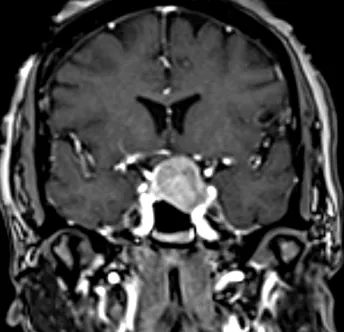

Pre- and Post-Op Pituitary Macroadenoma

Pre Op Pituitary Tumor Image 1

Pre-Op Image of Pituitary Tumor